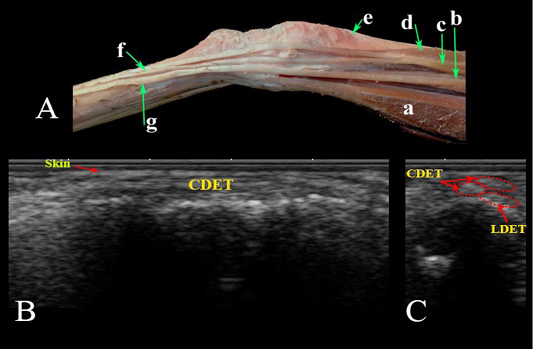

Lateral aspect of the carpal region. (A) Photomacrograph. Ultrasonographic imaging of the dorsolateral aspect of the carpal region: (B) LS and (C) TS. a- Ulnaris lateralis; b- Lateral digital extensor M.; c- Common digital extensor M. lateral belly; d- Common digital extensor M., medial belly; e- Extensor carpi obliqus M.; f- Tendon of common digital extensor; g- Tendon of lateral digital extensor M; LDET- Lateral digital extensor tendon; CDET- Common digital extensor tendon.